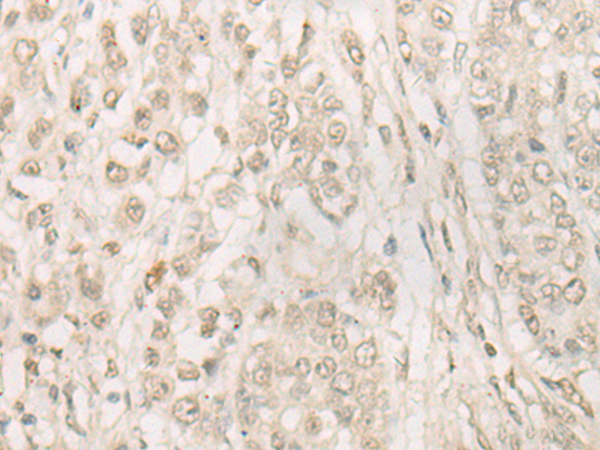

ELISA, WB, IHC

IHC positive control:

Human cervical cancer and Human colorectal cancer

IHC Recommend dilution:

20-100